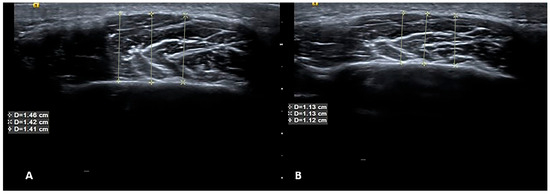

2.2. USG Imaging

2.3. USG Image Segmentation